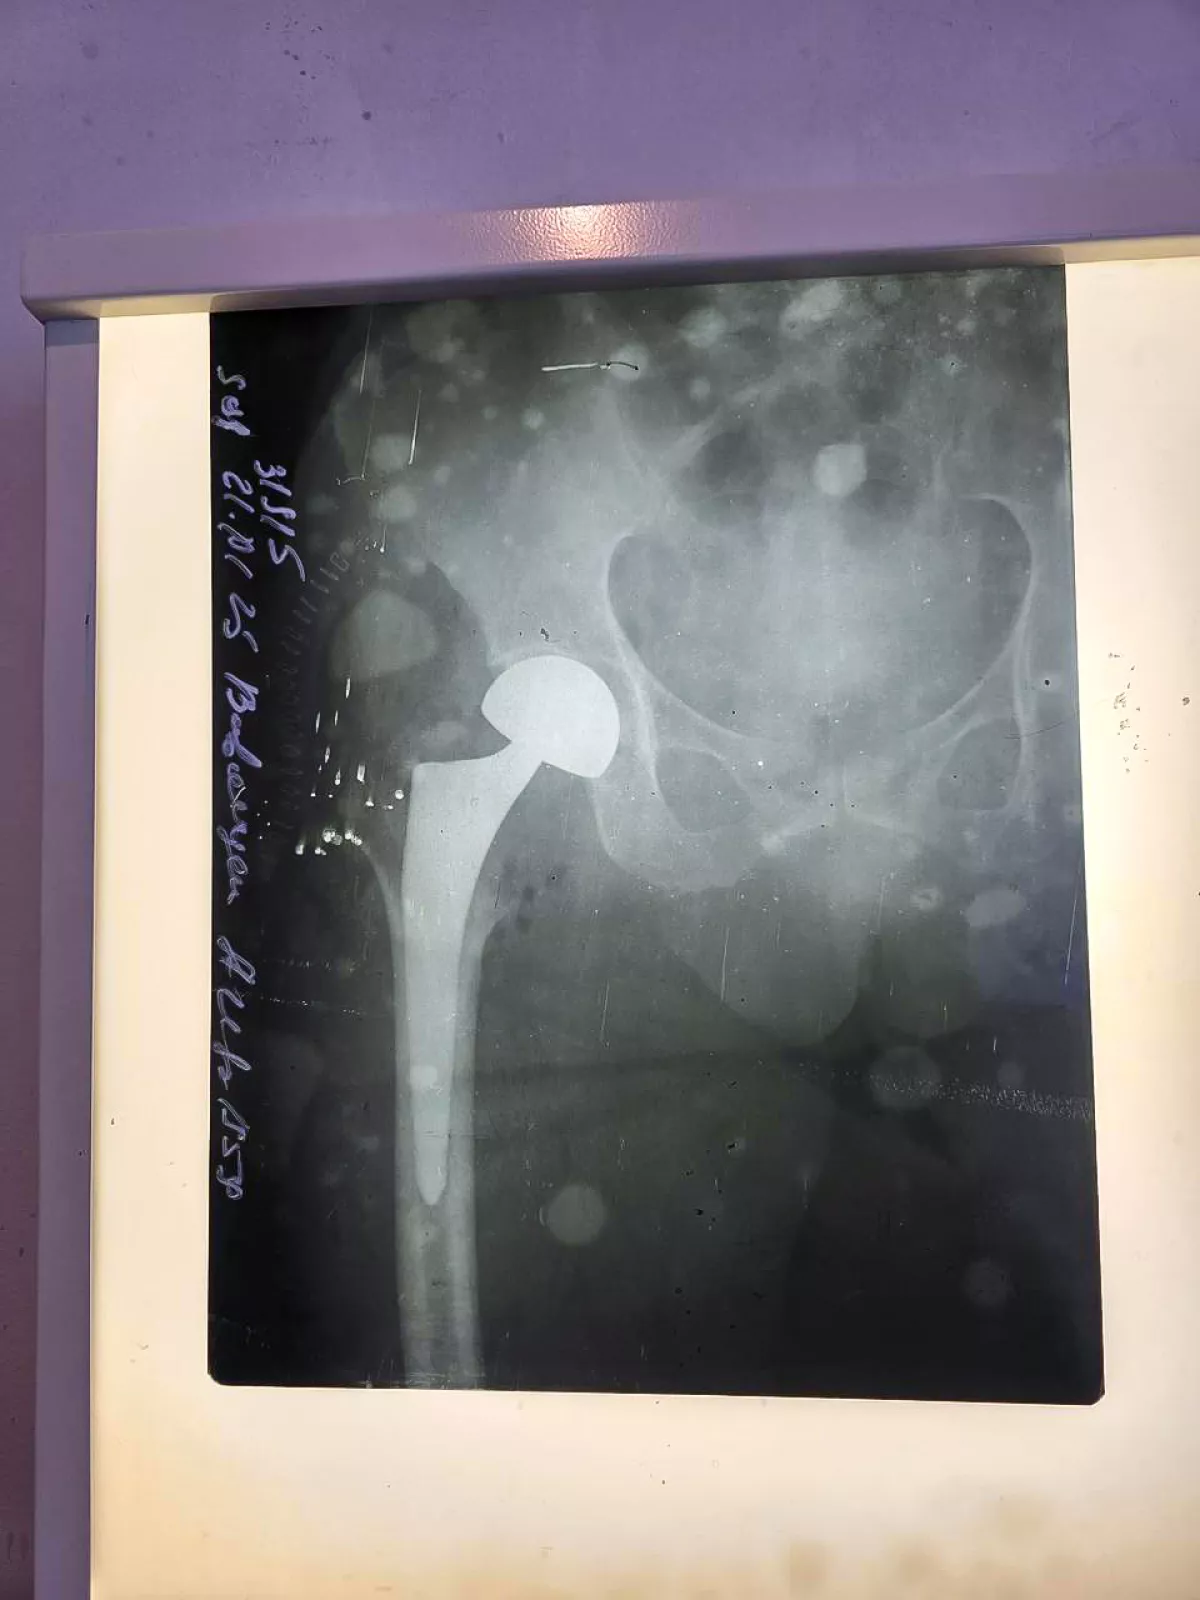

Число медучреждений Азербайджана, выполняющих операции по эндопротезированию, достигло 10-ти ФОТО

Число медицинских учреждений, подведомственных TƏBİB и выполняющих операции по эндопротезированию, достигло 10-ти.

Как сообщает Caliber.Az, с сегодняшнего дня операции по эндопротезированию выполняются и в Сабунчинском медицинском центре. Первая операция выполнена для 66-летнего пациента в рамках обязательного медицинского страхования.